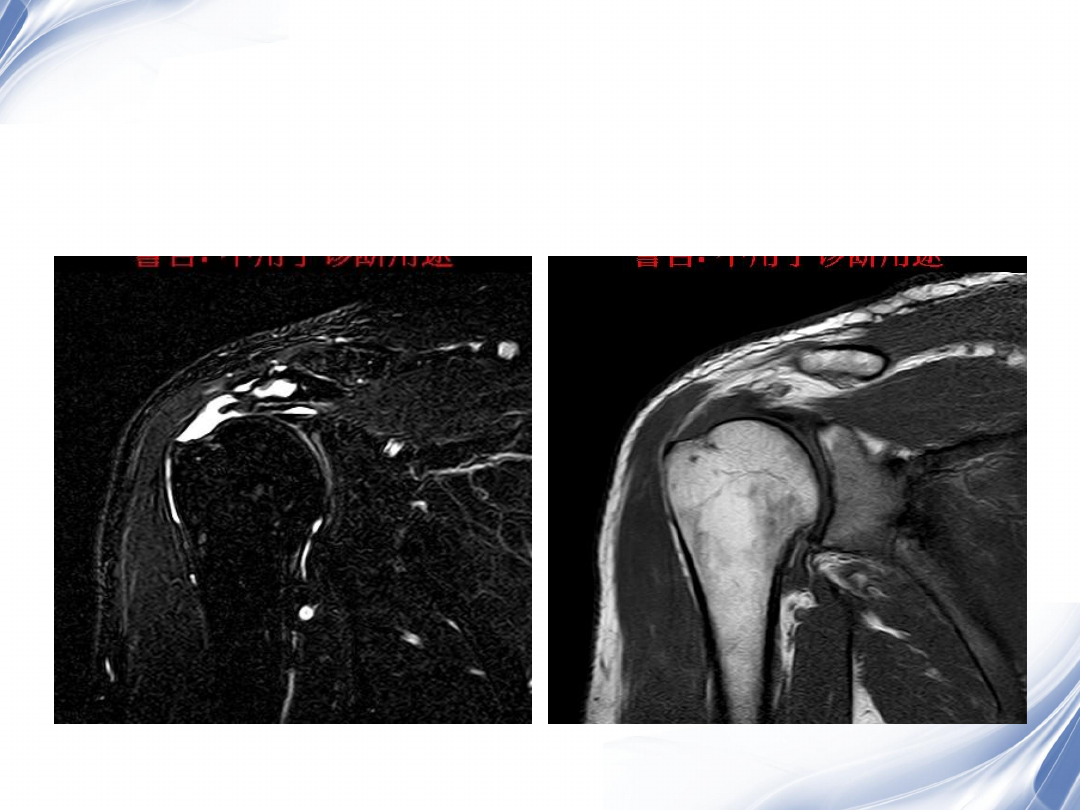

巨大肩袖损伤(冈上肌)

T2WI

T1WI

36

术后

2

37